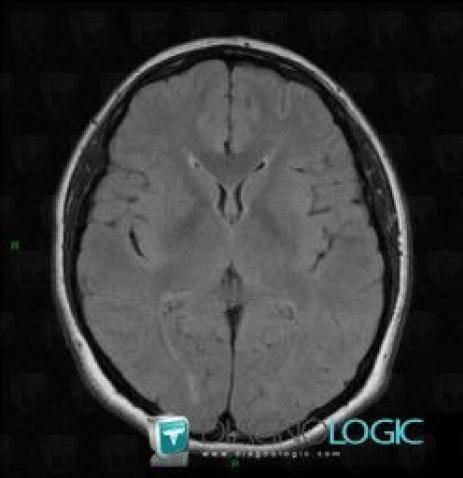

Télangiectasie capillaire, Hémisphères cérébraux, IRM

Voici les informations spécifiques à l'image clé ci dessus:

- Diagnostic Télangiectasie capillaire, Localisation(s) Hémisphères cérébraux, comportant les gammes Lésion intracérébrale en isosignal T2 ou FLAIR